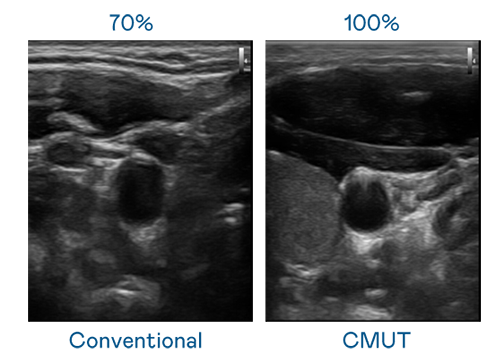

CMUT 技术是一种用电容式微机电元件来产生超音波讯号的技术。与传统 PZT 压电式技术相比,CMUT 频宽增加 30%,更宽频的超音波讯号让影像解析度大幅提升,是实现高影像品质医疗超音波扫描、促进精准医疗发展的关键技术。

超音波影像的解析度高低,首先取决于探头能发出的讯号频宽。EVO真人视讯 CMUT 可提供高清晰的超音波讯号,提供高频宽、高灵敏度、影像纹理细节更高的超音波影像,协助医护人员缩短影像判读时间及利用精准的医疗影像进行诊断。